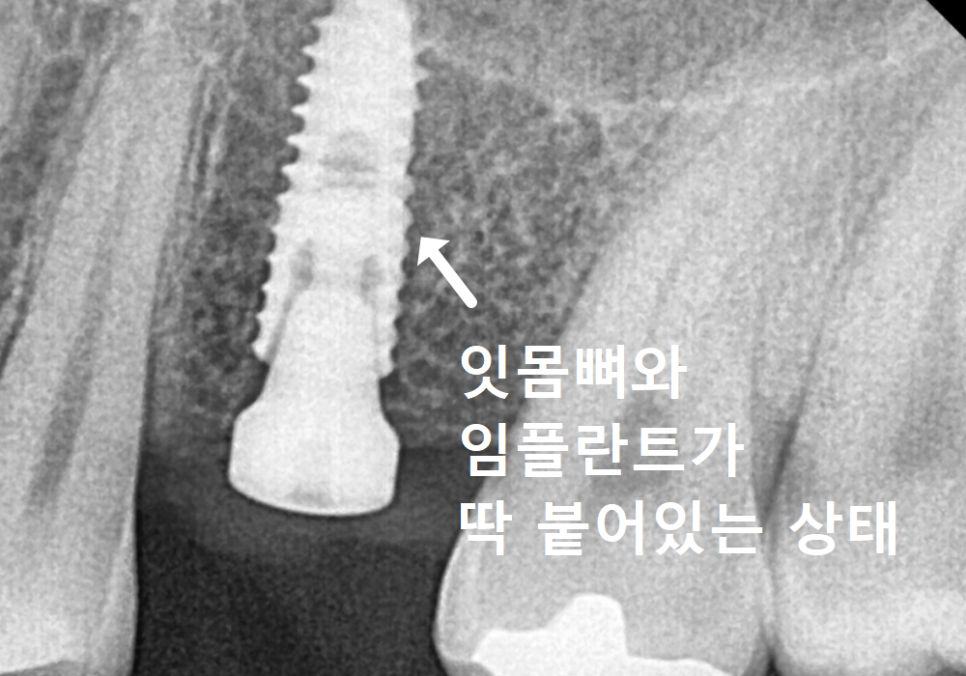

상실되었던 어금니 임플란트 역시

정확한 위치에 식립되어 튼튼하게 완성되었답니다.

260404

임플란트는 한 번 뼈에 고정되면

이동이 힘들기 때문인데요.